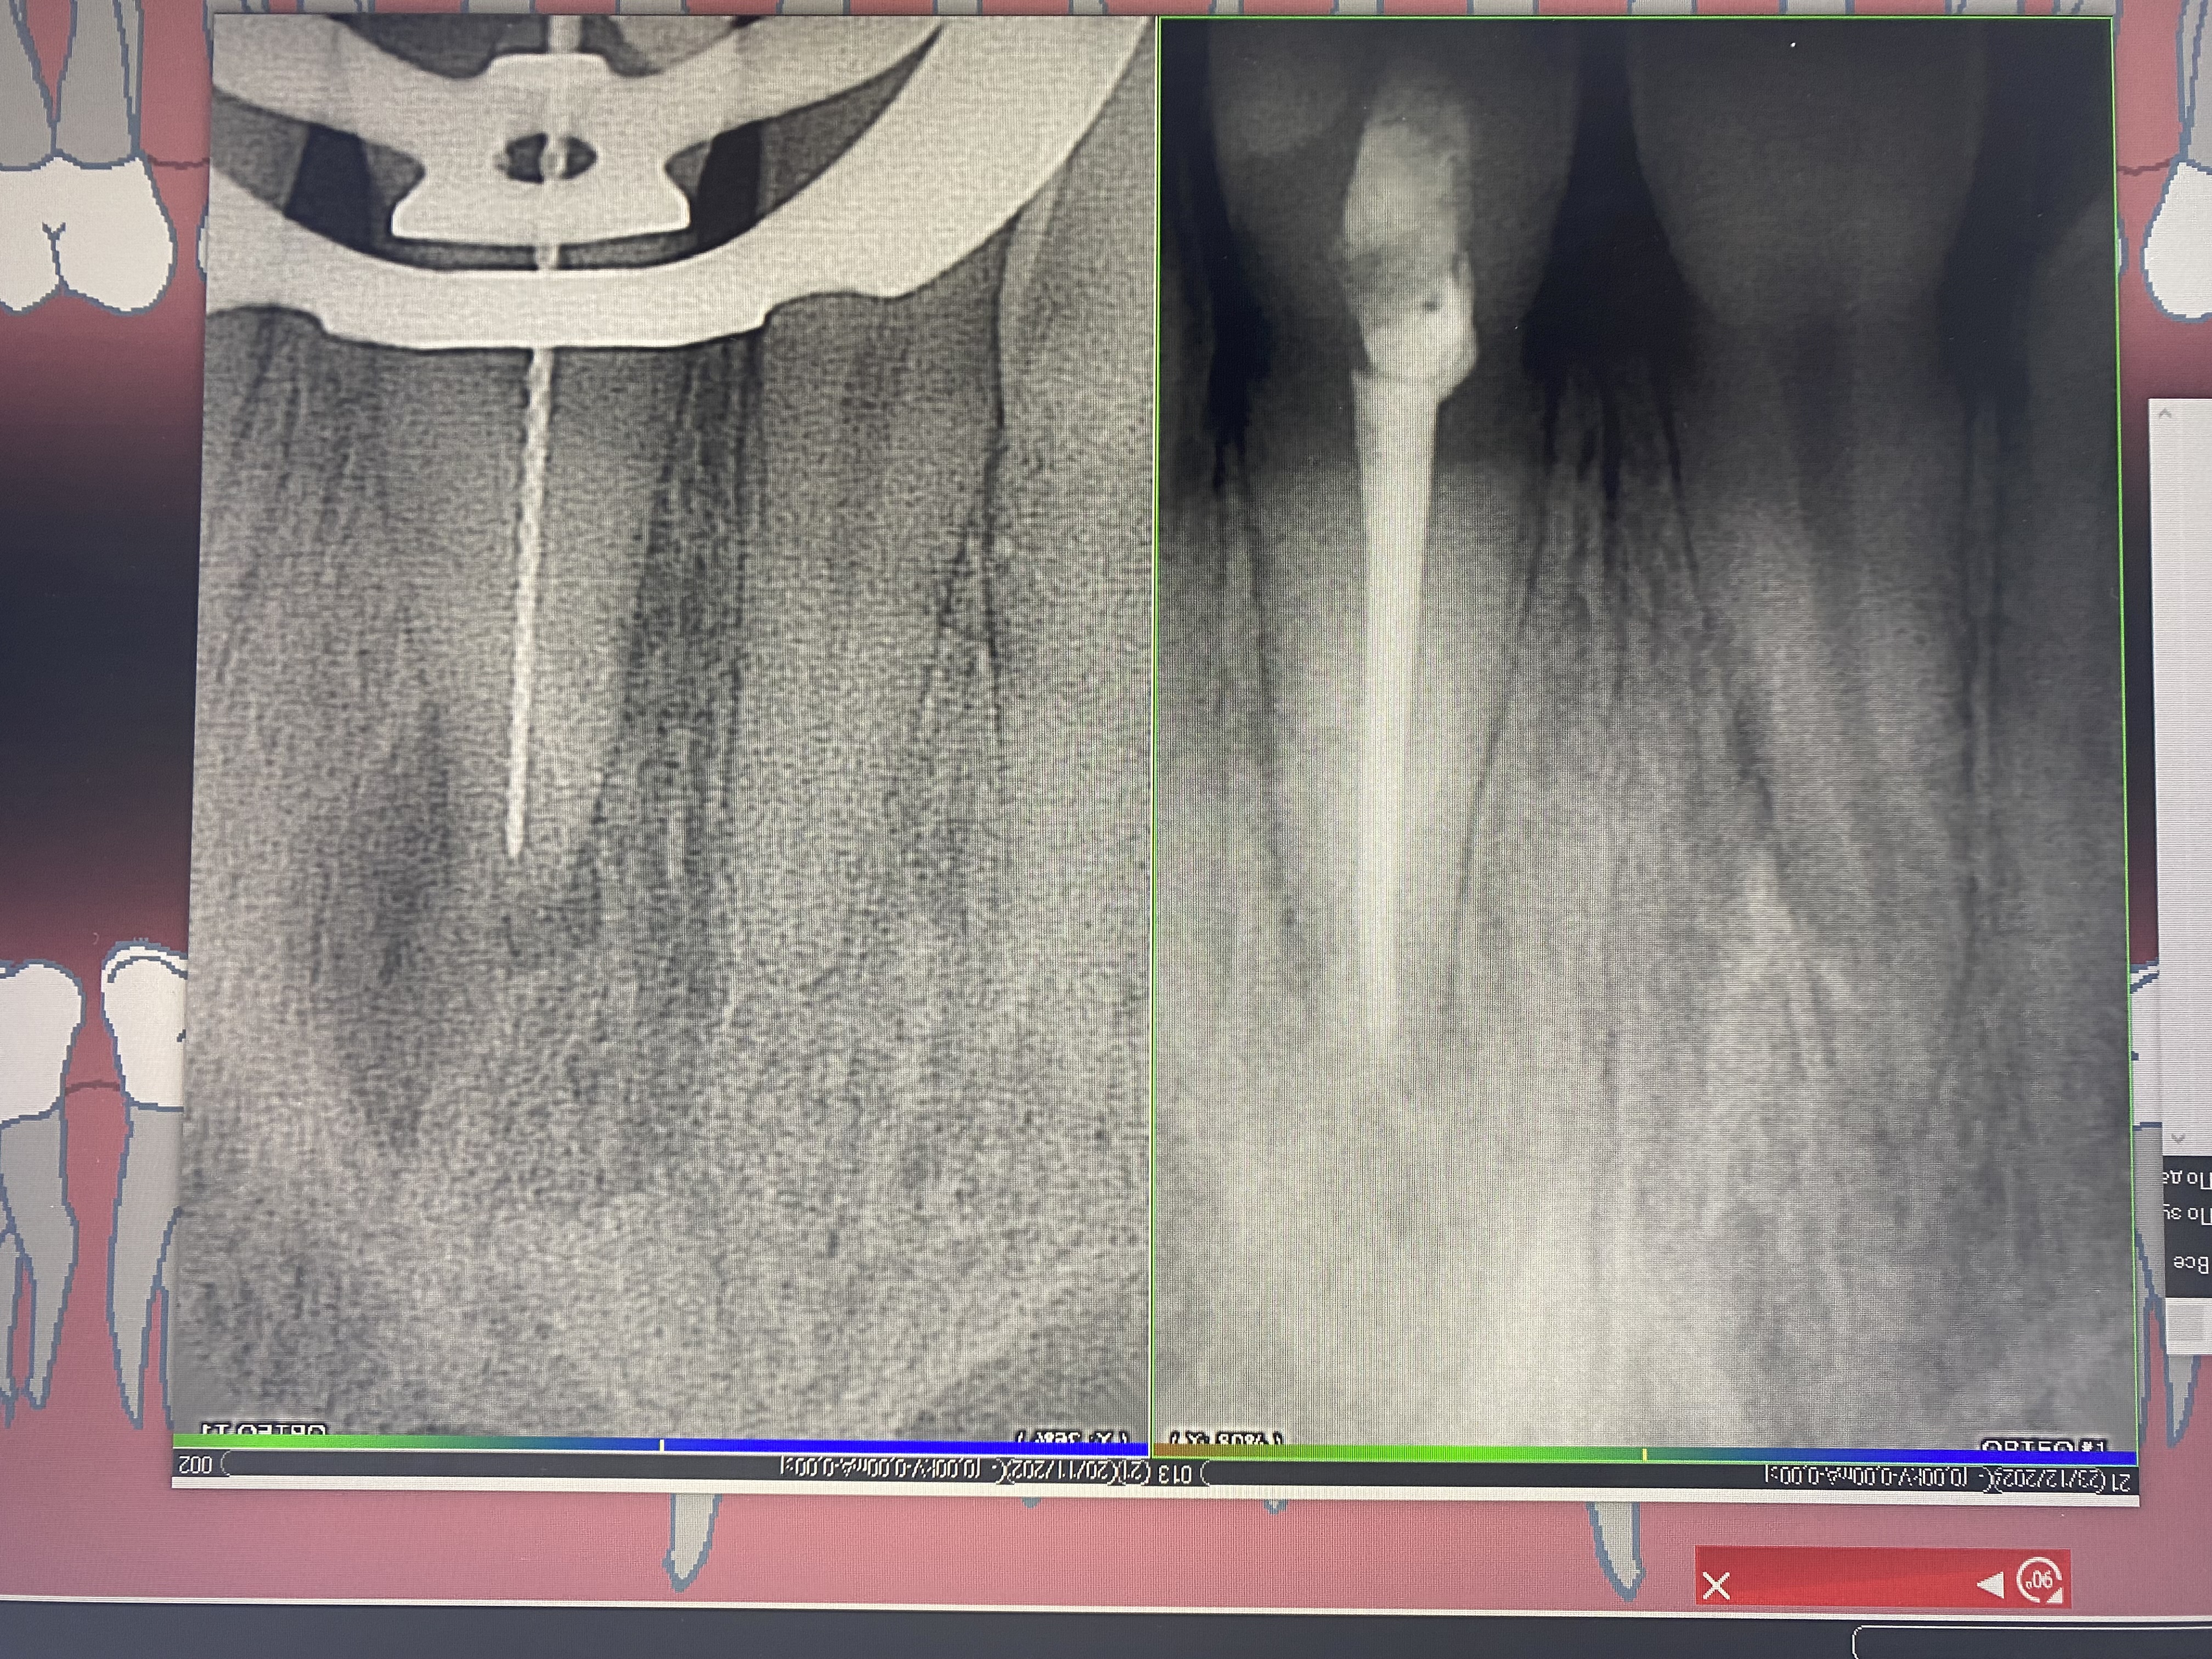

- Владение современными методиками пломбирования корневых каналов, обработки и распломбировки многокорневых зубов любой степени сложности

- 2019г.курс "Повторное эндодонтическое лечение. Консервативные и хирургические методы"

- 2014г.Перелечивание ортоградная ревизия). клинические решения и техника".

- 2014г.обучение в Medical consulting group "Сложная эндодонтия: трещины, переломы, открытый апекс. Предотвращение, лечение."